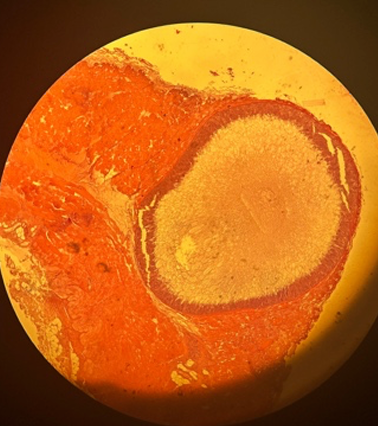

Echinococcus multiocularis